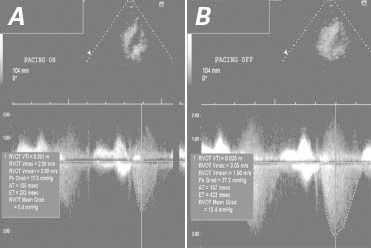

Angiography was performed to measure and characterize the gradient across the RVOT. There was a hemodynamically significant gradient of 54 mmHg (mean, 33 mmHg). When the patient coughed and then performed the Valsalva maneuver, the peak gradients increased to 94 mmHg and 106 mmHg, respectively. Potentiation of the peak gradient across the RVOT was observed after a premature ventricular contraction (Fig. 7). Because of the patient's unexplained syncope, a cardioverter-defibrillator was implanted for the primary prevention of sudden cardiac death. An atrial lead was also implanted to accommodate any future need for atrioventricular synchronous pacing. Transthoracic echocardiography was performed to evaluate the effect of RV pacing on the RVOT gradient. The peak gradient across the RVOT was 17 mmHg with RV pacing and 37 mmHg without RV pacing (Fig. 8).

Fig. 8 Transthoracic echocardiograms show gradients across the right ventricular outflow tract. A) With pacing, the peak gradient was 17 mmHg at 72 beats/min. B) Without pacing, the peak gradient was 37 mmHg at approximately 72 beats/min.

AT = acceleration time; ET = ejection time; Grad = gradient; Pk = peak; RVOT = right ventricular outflow tract; Vmax = maximum velocity; Vmin = minimum velocity; VTI = velocity time integral

Right ventricular involvement has been reported in hypertrophic cardiomyopathy; however, its prevalence is variably described.1 Dual-chamber pacing has produced favorable hemodynamic effects in patients with symptomatic LVOT obstruction.2 In comparison, RV pacing reduced the gradient across our patient's RVOT.